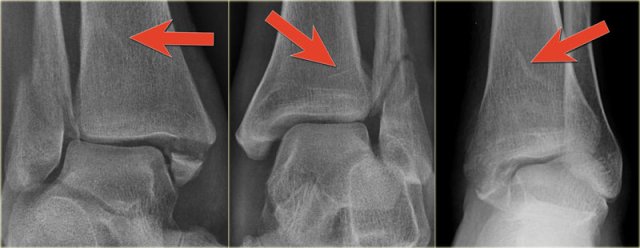

Triplane fracture Triplane fracture

At first this looks like a Weber B fracture with an oblique fracture in the fibula as seen on the lateral view (black arrows).

Notice however that this fracture line stops at the level of the epiphyseal plate.

So this is the fracture of the metaphysis in the coronal plane.

On the AP-view there is a lucency within the epiphysis, which is the epiphyseal fracture in the sagittal plane.

Notice also that the medial epiphysis is already closed, while the lateral portion is still open(blue arrows).

We have to assume that there is an epiphysiolysis of this lateral portion.

Here another example.

There is only a small metaphyseal fragment, which is usually the case (red arrow).

The fracture through the epiphysis is indicated by the blue arrow.